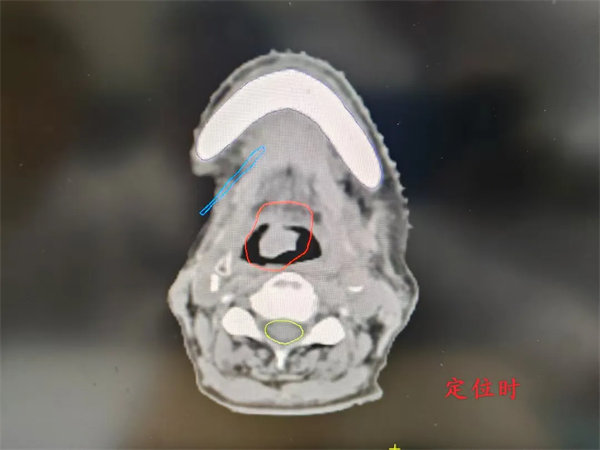

借助TOMO精準治療優勢,綜合評估后,近期,放射治療科為一例舌癌復發轉移、憋氣明顯的患者進行了放射治療,僅僅經過四次放療,老人家憋氣的癥狀就有了明顯的改善,圖像引導的結果顯示,病灶也同步在逐漸縮小。

完成放射治療后,復查CT,如下